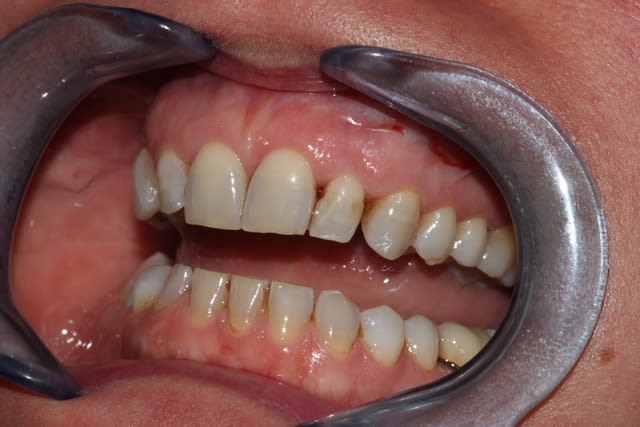

image 2: combo strat. après endo tout en Gaenial: A2/A1/TE/JE et tescera blanc. Photo prise à 7 jours. Patient moyennement satisfait.

image 3: retrait de la couche de JE, puis retouche au TE et Renamel LI (light incisal), avec reprise de la morphologie, photo prise à la fin du travail, d'où la déshydratation visible sur 11 et 22. A voir dans 7 js.

Le Renamel est non seulement plus lumineux mais il est aussi beaucoup plus facile à polir (c'est même mieux que le Micerium HFO, mais bon tenu dans le temps à voir) et offre une belle palette de possibilité pour jouer avec les microgéographies, l'utilisation de "cire" de modelage (ici Micérium...on se refait pas ;-)), est un plus pour assouplir ce composite, et bizarrement la spatule à suffit au modelage, et il n'y pas eu besoin du pinceau silicone.

Bon le patient n'est toujours pas satisfait, d'autant plus que son hygiène est déplorable (ça saute pas aux yeux à première vue), et qu'après un détartrage/surfacage autour de la 11, on se retrouve avec un retrait papillaire important. On va lui apprendre à se brosser les dents, en espérant que l'esthétique rose récupère, il est jeune alors avec un peu de bol!